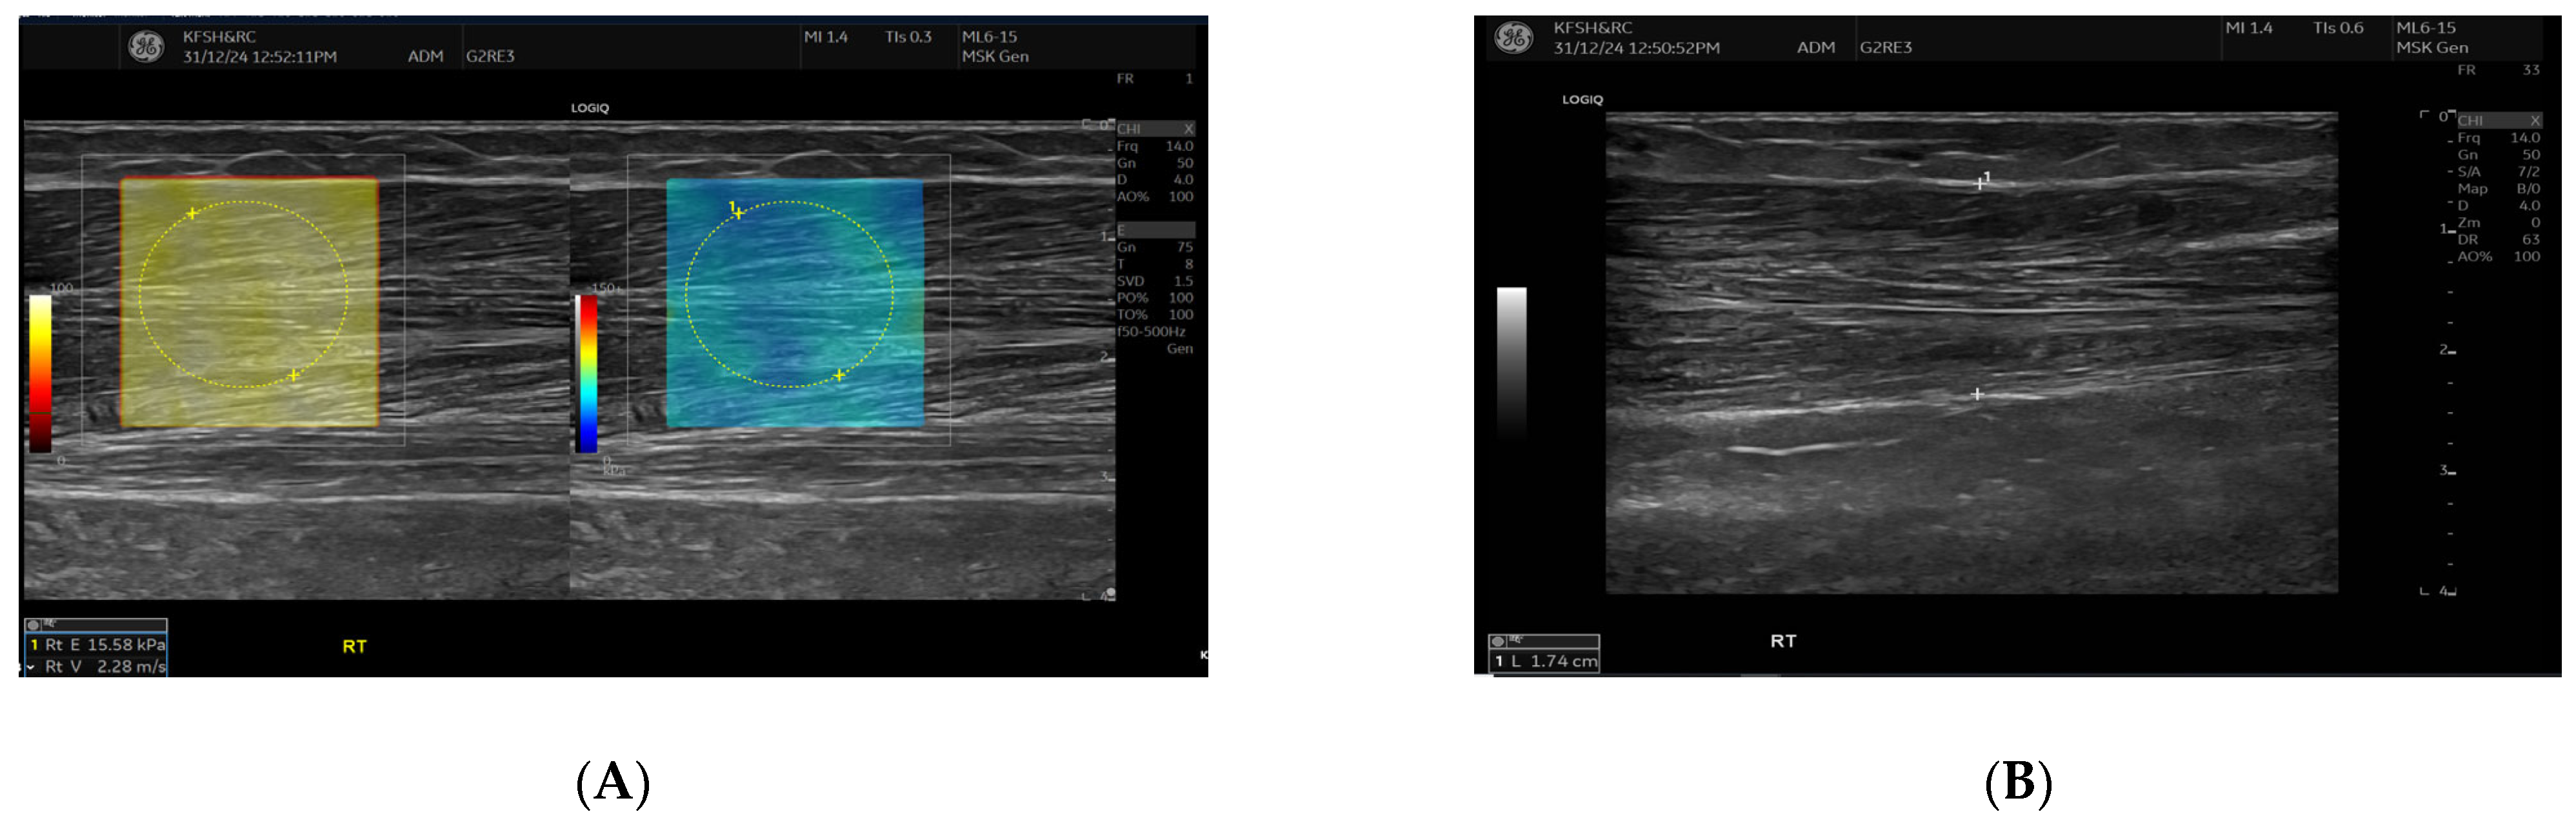

SWE measurements were acquired using a GE LOGIQ E10 (GE HealthCare, Chicago, IL, USA) system equipped with an ML 6-15 D linear transducer (frequency 6–15 MHz). Depth settings were standardized at 2.5–3.5 cm depending on muscle thickness. Each ROI was circular with a 5–7 mm diameter, placed centrally within the elastograms, avoiding fascia, vascular structures, and visible artefacts. Stiffness values were recorded in both kilopascals and metres/second, although statistical analyses were conducted using shear-wave velocity (m/s) for consistency. Frames with motion or colour dropout were discarded and reacquired. Muscle stiffness and thickness were evaluated in the biceps brachii and brachioradialis muscles, located proximal to the AVF site, Figure 1 and Figure 2. SWE imaging provided both Colour-coded elastograms and quantitative stiffness measurements (m/s; Figure 3). Participants were examined supine, with the shoulder in neutral rotation, the elbow extended to approximately 10–20°, and the forearm supinated. This minimized passive tension, which can influence shear-wave velocity. The transducer was positioned perpendicular to the muscle fibres, capturing measurements from the proximal, middle, and distal regions for comprehensive analysis. Measurements were taken before the haemodialysis to avoid intravascular volume shifts, with each parameter recorded three times and averaged for precision. Scans were performed by an experienced sonographer and verified by a radiologist, minimizing bias. A preliminary review of some patient records was conducted to refine data collection tools before the main data collection.

Figure 1.

This figure shows the Ultrasound assessment of stiffness near the arteriovenous fistula site (A) and brachioradialis muscle thickness (B). Shear wave elastography images (A) obtained at the fistula side demonstrate quantitative stiffness mapping within a defined region of interest, with stiffness expressed in velocity in metres per second (m/s). B-mode image (B) showing brachioradialis muscle thickness measurement at the contralateral (right) arm.